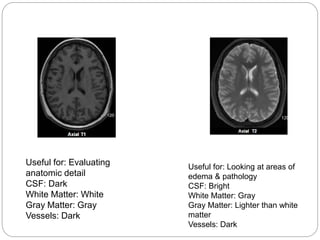

T1W/T2W IMAGES

Useful for: Evaluating

anatomic detail

CSF: Dark

White Matter: White

Gray Matter: Gray

Vessels: Dark

Useful for: Looking at areas of

edema & pathology

CSF: Bright

White Matter: Gray

Gray Matter: Lighter than white

matter

Useful for: Evaluating anatomic

detail

Useful for: Evaluating for BBB breakdown

in the setting of tumor, infection, MS etc.

Vessels: Brigh

Useful for: Looking at areas of edema &

pathology

Gray Matter: Lighter than white matter